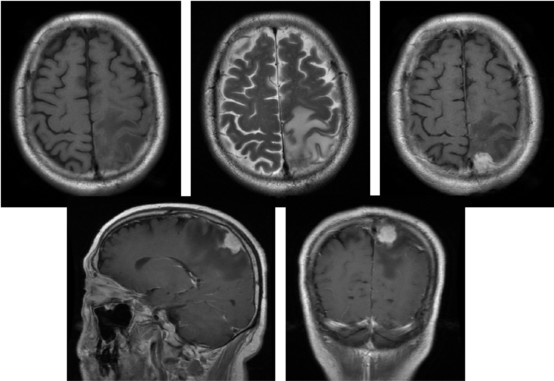

入院后复查头颅MRI增强(图1),影像学报告提示:左顶部矢状窦旁占位,考虑黑色素瘤或侵袭性脑膜瘤可能,不能完全排除转移瘤。

图1. MRI增强显示左顶部矢状窦旁占位,周边水肿带形成,考虑脑膜瘤可能。